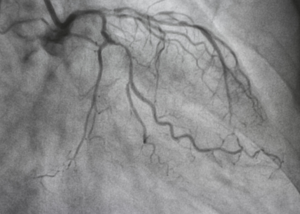

Angiography: When and Why It's Needed | Dr. Mahesh Kharade

Heart diseases are among the leading causes of mortality worldwide. Early diagnosis plays a crucial role in preventing severe complications like he...

Coronary Artery Disease (CAD) is one of the leading causes of heart-related complications worldwide. It occurs when the coronary arteries, responsi...

Coronary Angioplasty: Procedure and Benefits | Dr. Mahesh Kharade

Heart disease is one of the leading causes of death worldwide, and blocked coronary arteries are a major contributor to heart attacks and other car...